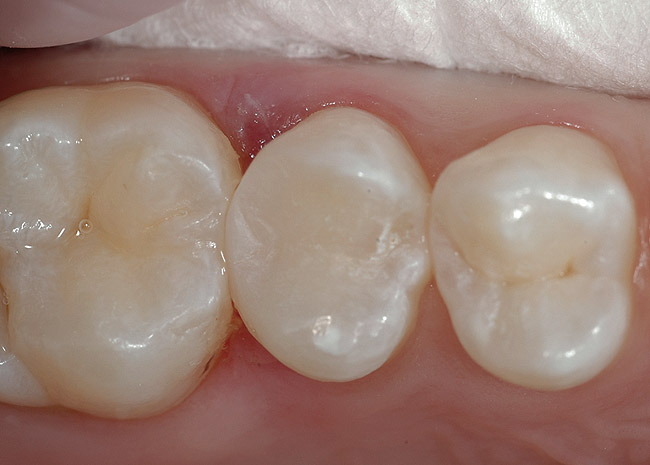

Figure 9  Appropriate degree of surface moisture after acid-etching and rinsing, prior to primer placement when using a total-etch system. Note no puddles of water, yet dentin is visibly moist.

Figure 9

Figure 12  Excess water blotted out with a cotton pellet to avoid over-drying.

Figure 12